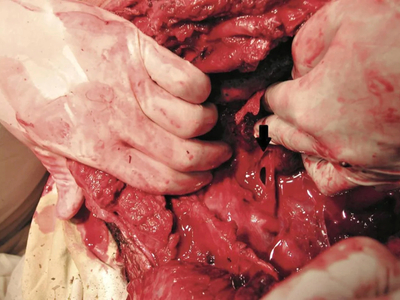

Complex thoracic impalement

It's a miracle he survived